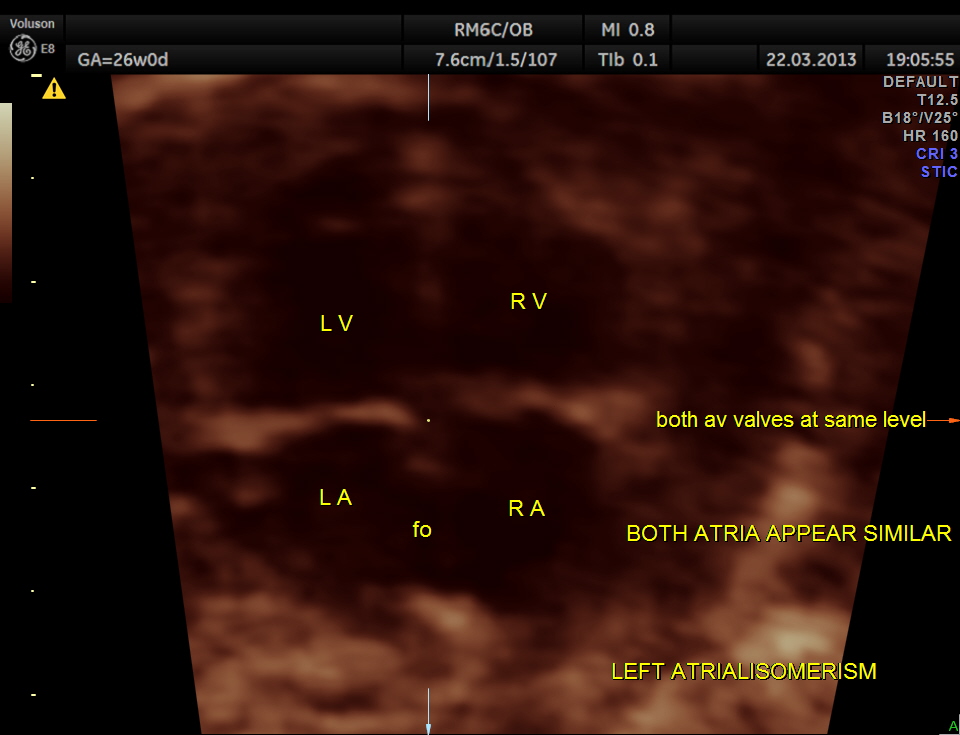

A V VALVES are at the same level

STIC image shows ATRIO VENTRICULAR SEPTAL DEFECT ( ENDOCARDIAL CUSHION DEFECT )